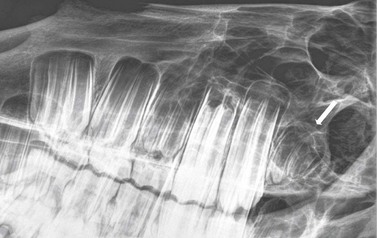

image image image

Fig. 13.37 (A) Maxillary cheek tooth row of a miniature Shetland pony with marked dysplasia of the 109, 110, and 111 and a corresponding wave mouth on the mandibular row. (B) Markedly enlarged, radiodense, dysplastic 110, which has displaced the reserve crowns and apices of 111 and 109 caudally and rostrally, respectively. (C) Abnormally small 302. The deciduous 702 remnant is retained (arrow).